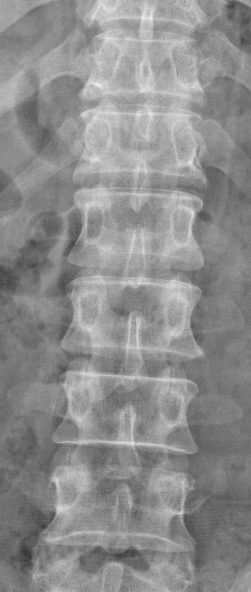

主诉:左下肢麻痛半年,加重伴乏力2周。 病史:患者半年前无明显诱因出现左下肢麻痛,腰部疼痛不明显,久站后有酸胀感。加重伴乏力2周;患者目前无二便失常。患者一般情况尚可。

体查:脊柱无明显畸形侧凸。各棘突及棘旁无明显压痛;左下肢肌力较右侧稍减弱,余四肢肌张力、感觉等无明显异常;双侧膝反射、踝反射无明显异常。病理征未引出。 辅助检查:三大常规、血生化检查未见明显异常,主要脊柱影像学检查如下,请参阅。

诊断:T12-L1椎管内肿物 治疗:患者入院后尽快完善相关检查,请神经外科会诊。经治疗组讨论,拟行“T12-L1椎管内肿物切除+钉棒内固定术”。

讨论:患者椎管内肿物,从影像学表现上看,主要考虑神经鞘瘤,但确诊需依靠手术的病理,同时根据患者的病理情况决定下一步治疗。